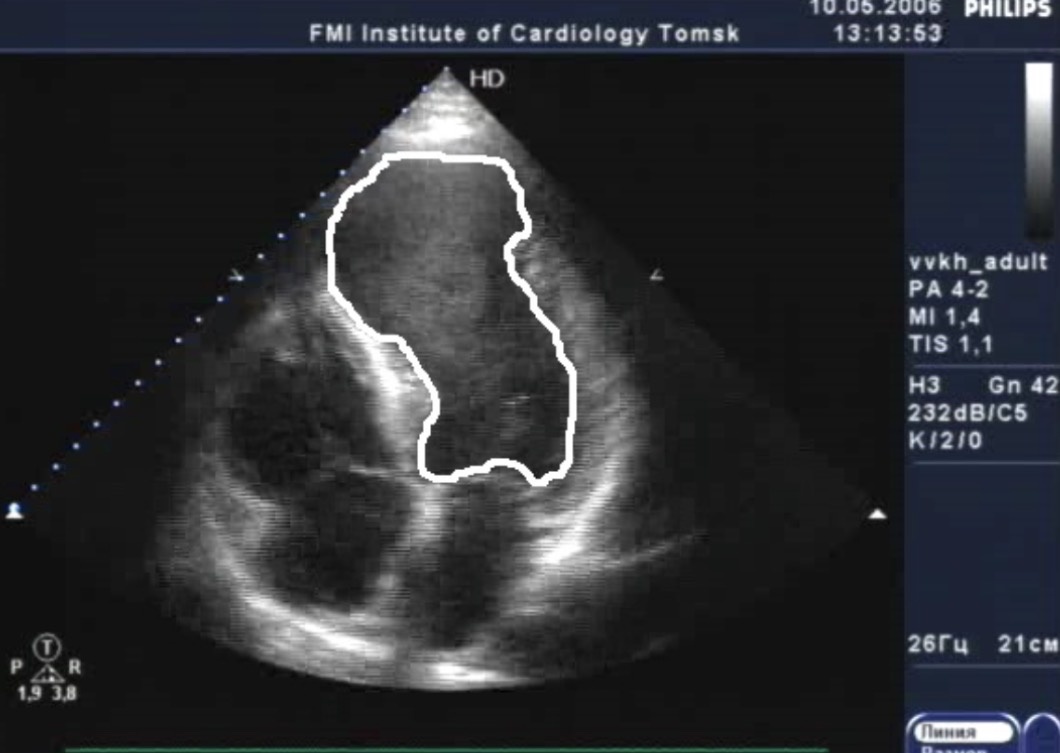

УЗИ сердца с аневризмой